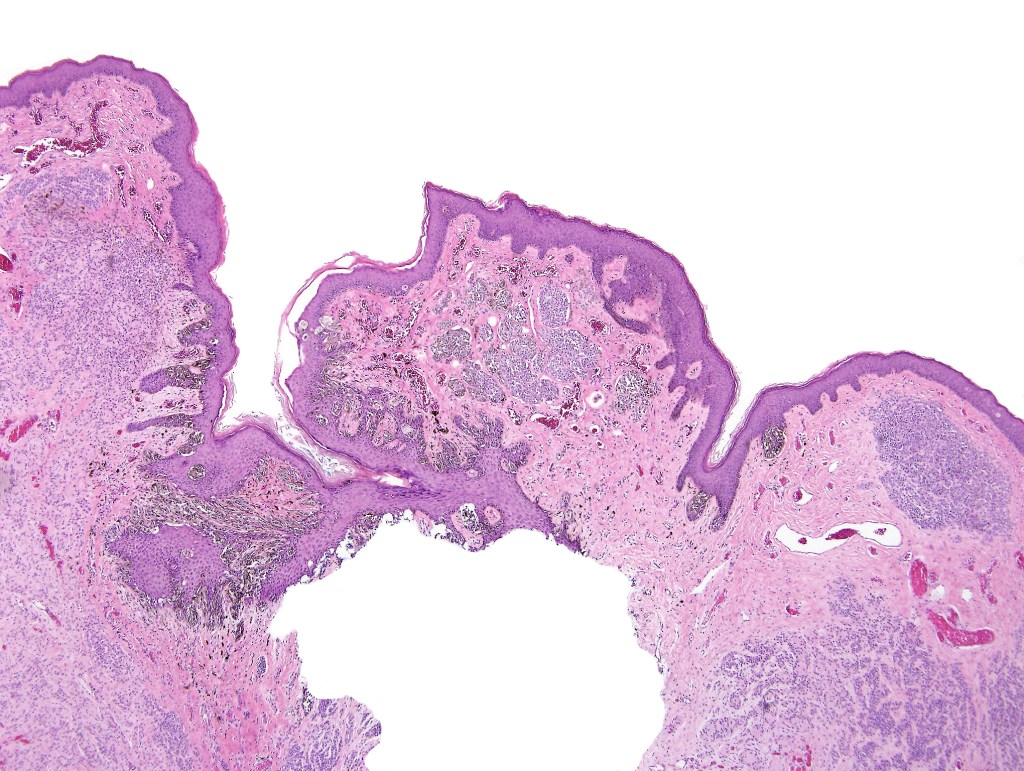

•Junctional/compound

•Large dyscohesive nests with retraction artifact, not restricted to the tips of the epidermal ridges

•Heavy pigmentation (sometimes gray/green)

•Bridging common, often over multiple rete ridges

•Central pagetoid spread